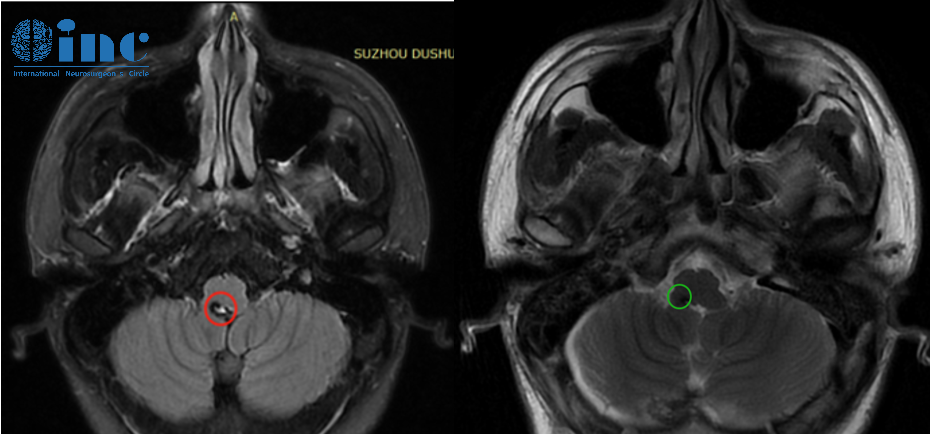

我们是从北京过来的,一位右侧基底节占位-海绵状血管瘤的柯女士通过INC预约来到巴教授苏州独墅湖医院咨询室。症状主要还是从头部、胳膊到后背,腿一直到脚底麻的感觉,偶尔脸部...